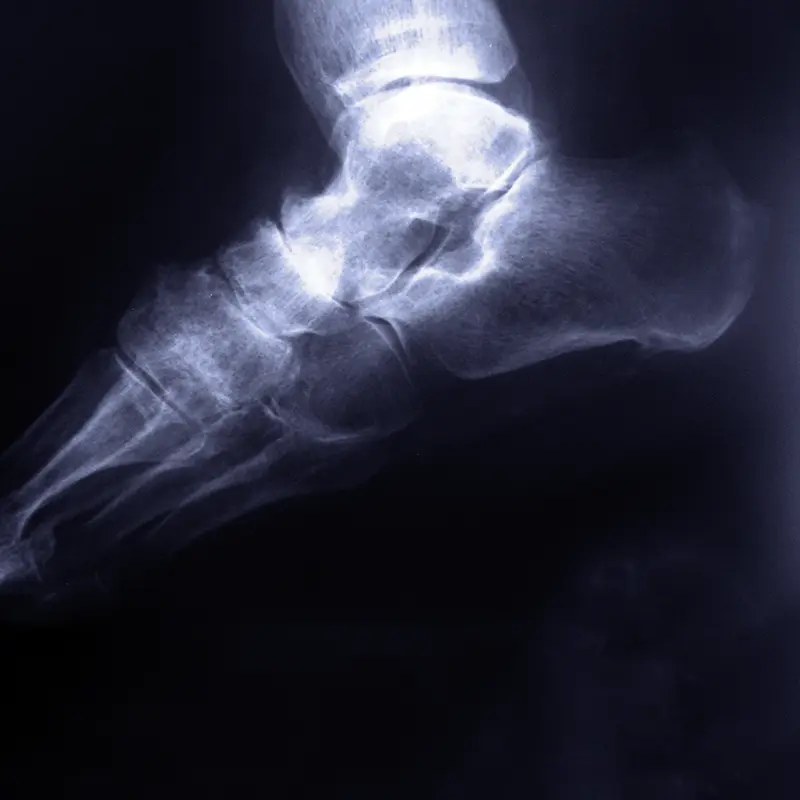

Las patologías que afectan a estas zonas del pie suelen tener un componente biomecánico importante y, en muchos casos, una evolución prolongada en el tiempo.

Engloban problemas como:

- Fascitis plantar, cuando no responde a tratamientos conservadores.

- Atrapamientos nerviosos (túnel del tarso, neuropatía de Baxter).

- Tendinopatías (tibial posterior, tendón de Aquiles, tendones peroneos).

- Cirugías del retropié (pie plano, artrosis, huesos accesorios).

- Cirugía reconstructiva (tratamiento de deformidades complejas y secuelas de lesiones en el pie y tobillo).

En estos casos, la indicación quirúrgica se valora de forma individual, teniendo en cuenta la biomecánica del pie y el impacto real del problema en la vida diaria.